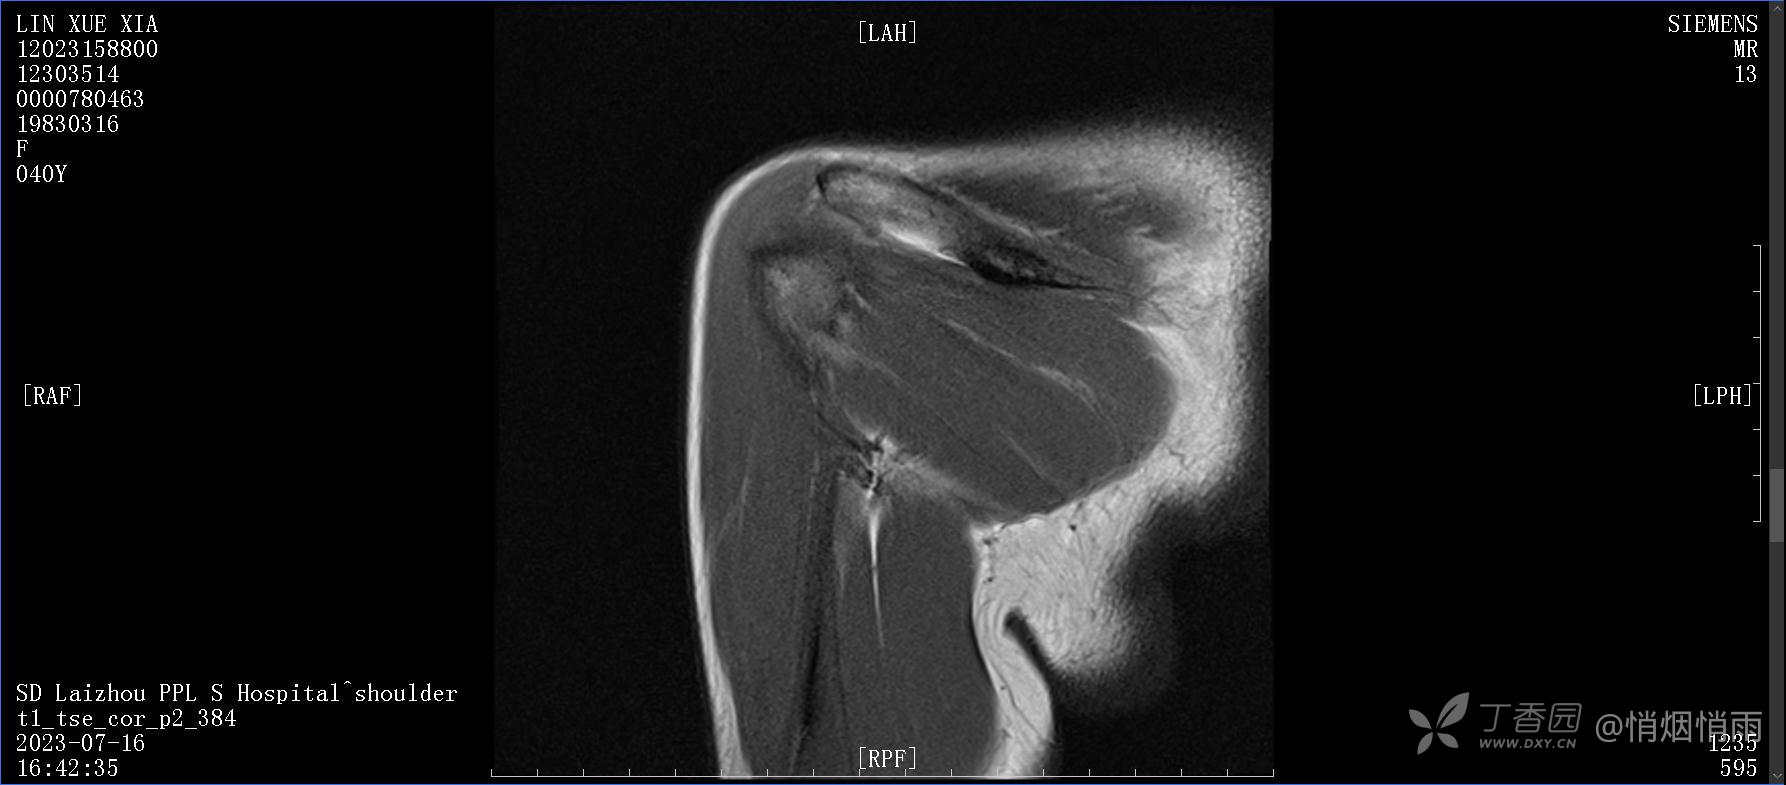

查体:右肩关节局部轻度肿胀,肩胛区压痛明显,痛处不固定,肩关节痛性活动受限,jobe test(+),lift -off test(+),中指、环指感觉较余指减退,余肢端感觉及血运情况可。

目前的诊断,暂时依据辅助检查诊为肩袖损伤,但是患者疼痛的性质和特点,却不是单纯的肩袖损伤所致。考虑过胸廓出口综合征,但是该疾病会出现肩胛区的疼痛吗?(由于考虑到费用的问题,没再进行下一步的检查)带状疱疹会有如此的症状吗?